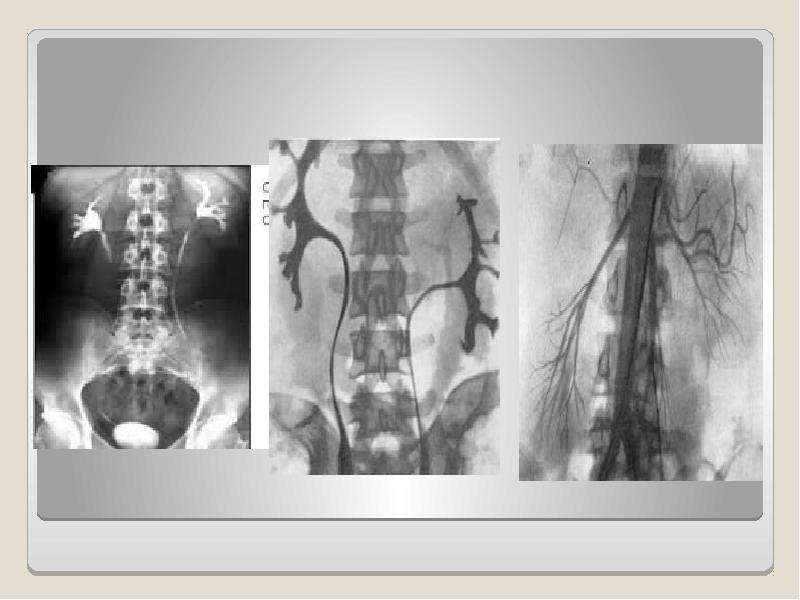

Экскреторная урография при нефроптозе: диагностические изображения